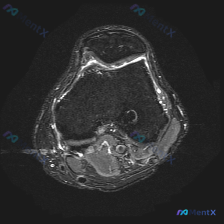

看到一份很有讨论价值的膝关节MRI病例,整理了影像发现和分析思路,和大家一起交流。 病例影像基本信息 这是一份膝盖MRI的轴位T2加权图像,扫描层面位于髌股关节滑车沟层面,可观察到以下明确异常: 1. 髌骨改变:髌骨后方关节软骨信号不均匀、局部T2高信号,软骨形态不规则、厚度变薄;髌骨边缘骨质可见高...

看到一份膝关节轴位MRI的读片资料,软骨异常是核心发现,整理了影像特征和完整分析思路,和大家分享讨论。 一、影像基本信息 这是膝关节髌股关节层面的脂肪抑制序列MRI(PD-FS或T2-FS),图像特征: 1. 髌骨、股骨皮质低信号,骨髓脂肪信号正常 2. 核心异常:髌骨后方关节软骨信号不均匀,局部高...

看到这个膝关节MRI的病例,整理了完整的影像表现和分析思路,分享给大家一起讨论。 一、病例基本影像信息 这是一份膝盖MRI T2序列轴位图像,扫描层面位于髌股关节层面,可见髌骨与股骨滑车关节面,评估结果如下: 1. 关节软骨:髌骨后方关节软骨为低信号带,髌股关节外侧面可见不均匀高信号改变,提示软骨磨...